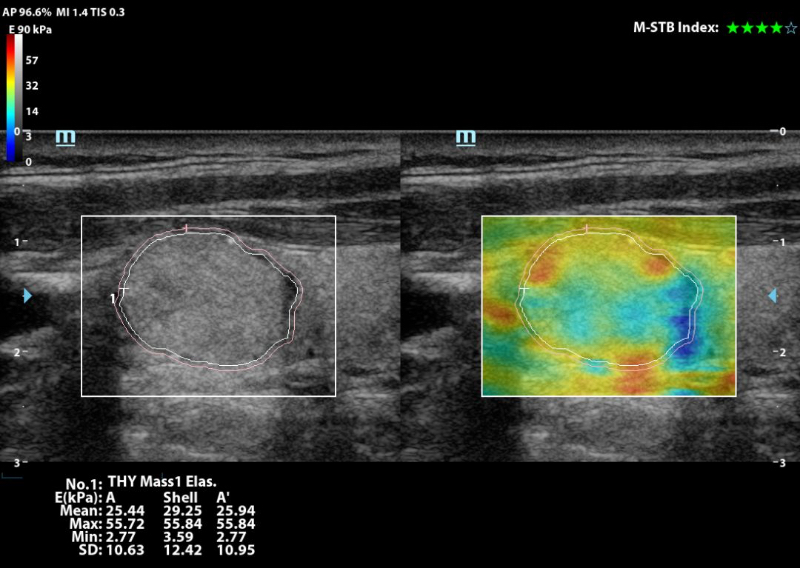

To meet such requirements, the DC-80 with X-Insight delivers the leading Sound Touch Elastography (STE) technology with real time 2D shear wave imaging and modulus quantification for easy tissue stiffness assessment in wide applications including liver, breast, thyroid and MSK. With the help of reliability map and motion stability index, STE provides quantifications with more accuracy and reproducibility for better diagnosis.

STE of thyroid nodule